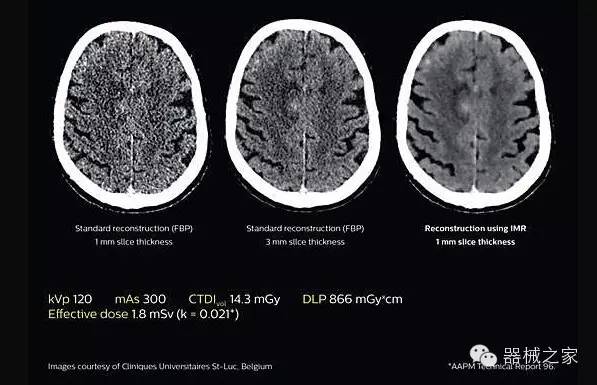

2.腦部顯影

透過數(shù)字化影真芯片DAS系統(tǒng)、球面微平板探測器技術(shù)和濾線柵技術(shù)等硬件技術(shù),整體提高探測器成像的能力,奠定低劑量條件下高清成像的基礎(chǔ);

應(yīng)用目前業(yè)界領(lǐng)先的新一代星光平臺iDose4 Premium及基于迭代基礎(chǔ)的O一MAR去除金屬偽影技術(shù),達(dá)成微量輻射下零偽影的高清晰成像;